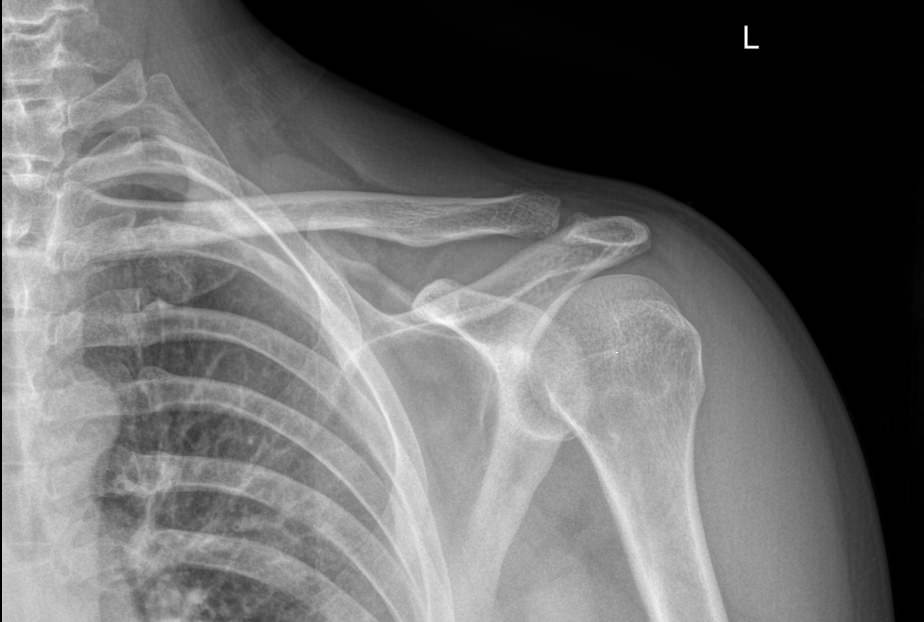

В случае травмы на снимке могут быть обнаружены:

• Отек мягких тканей;

• Расширение суставной щели;

• Ключица приподнята над акромионом;

• Перелом ключицы или клювовидного отростка лопатки;

• Изменения, свойственные дегенеративным процессам костной ткани.